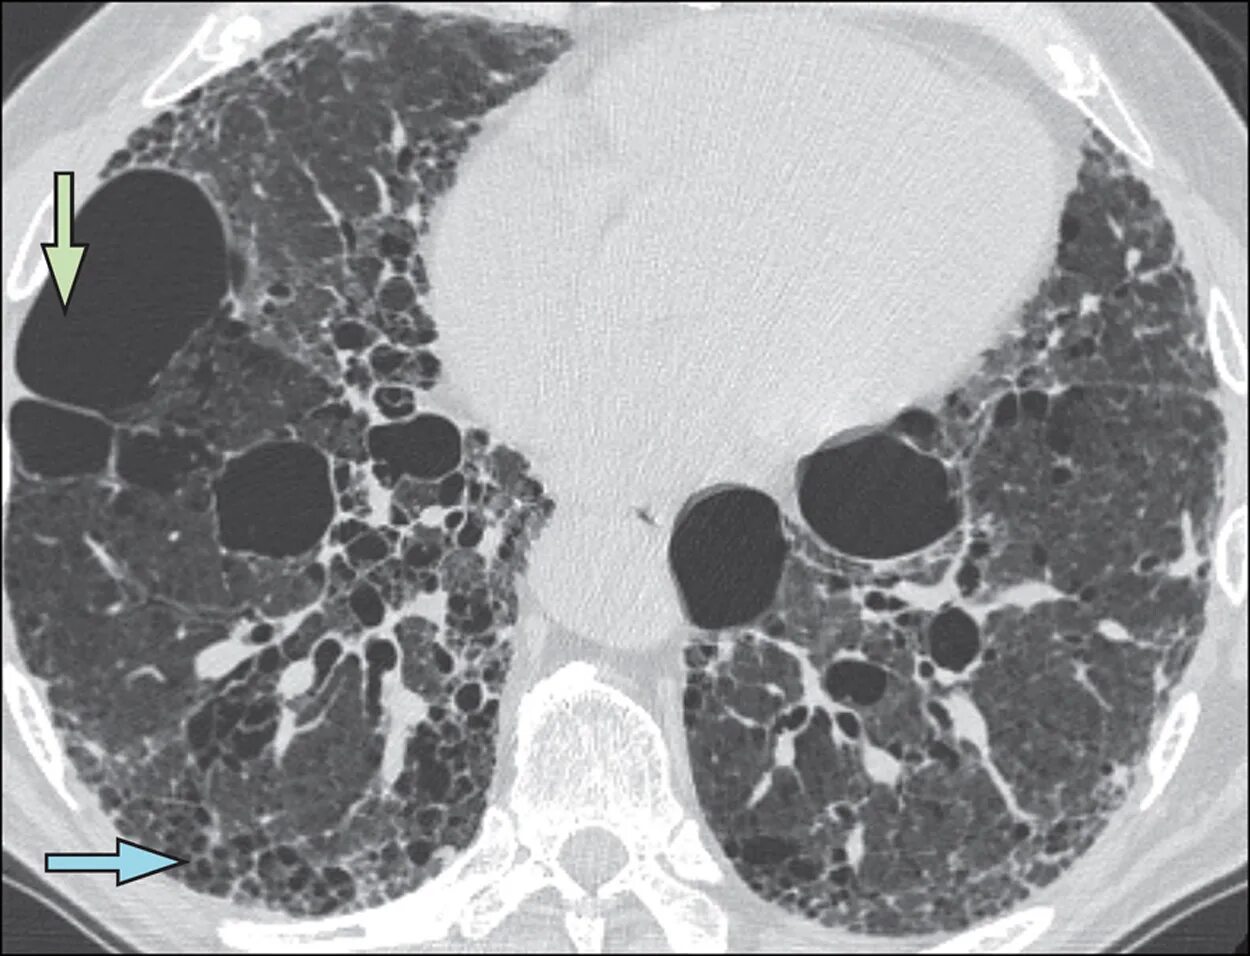

Как выглядит фиброз легких